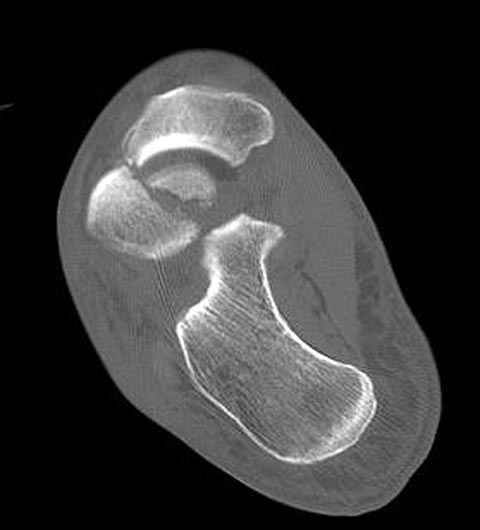

Уважаемые участники русского Ортофорума, поздравляю всех со всеми прошедшими праздниками: Новым годом, Рождеством, Hanukkah, Kwanzaa, желаю участникам всего наилучшего и здоровья.Повреждение таранной кости.Больной 81г автоавария, повреждение таранной кости, здесь снимки.

Вдогонку по поводу перелома таранной кости, больная 81, не страдает диабетом, перелом закрытый, в первый же день поступления ограничились временным наружным фиксатором (как на снимке).

Примеры на снимке...